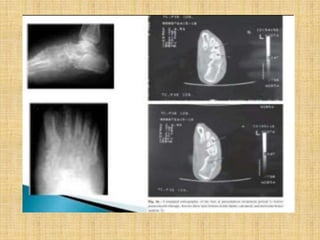

Imaging

• Plain x-rays assess for evidence of bone

involvement

• CT scan may be more sensitive in the early

stages

• MRI scans better assessment of the degree of

bone and soft tissue involvement; and may be

useful in evaluating the differential diagnosis

of the swelling .

Bone radiography

• Once mycetoma has invaded the bone, the

following changes may be observed:

• Cortical thinning is due to compression from

the outside by the mycetoma.

• Multiple lytic lesions or cavities may be large

and few in number with well-defined margins

(eumycetoma) or small and numerous with ill

defined margins(actinomycetoma).

• Osteoporosis may occur in late stages.

Ultrasonography

• Single or multiple thick-walled cavities with

hyper reflective echoes and no acoustic

enhancement

• In eumycetoma, the hyper reflective echoes

are sharp, corresponding to the grains in the

lesion.

• In actinomycetoma, the hyper effective

echoes are fine and closely aggregated and

commonly settle at the bottom of the cavities.